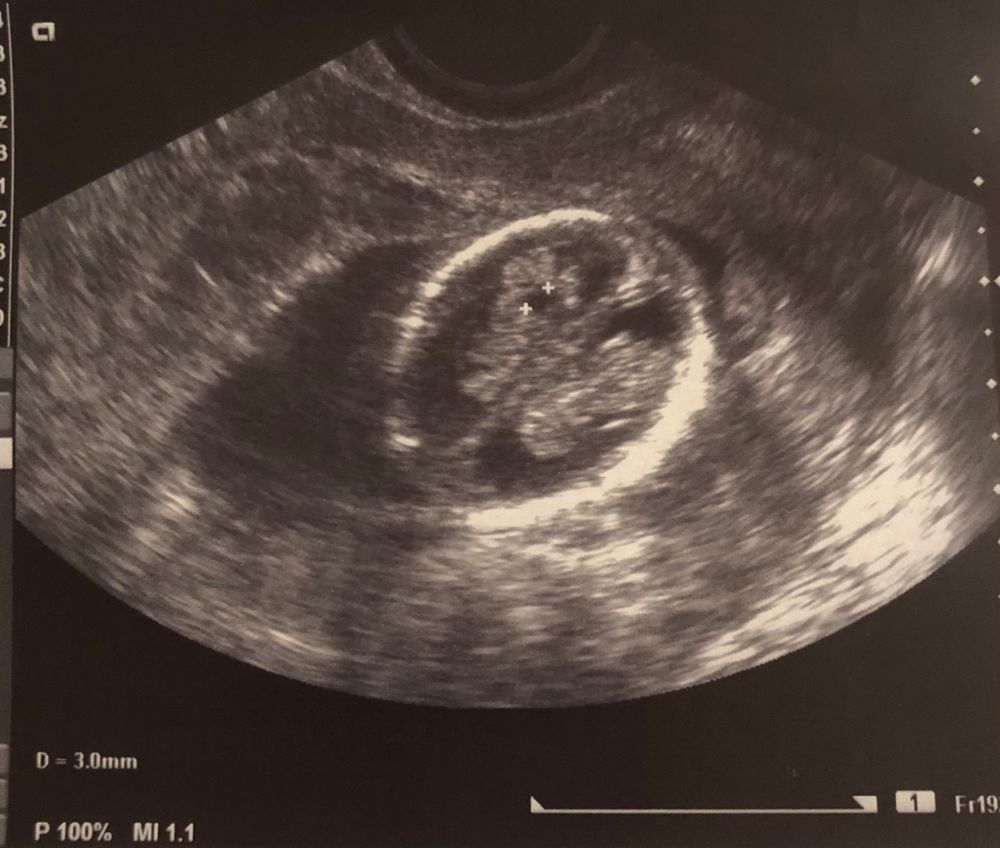

Киста сосудистого сплетения 😳

Такую кисту часто обнаруживают у деток, у нас на втором скрининге одна 3 мм кисточка, сказали не переживать вообще, она рассосётся, Скорее всего инфекция была, здесь я гуглила и у многих она была, рассосалась спокойно, так что не переживайте, все хорошо будет 😘

У моего второго сына по узи в 18 недель была ксс, сейчас специально нашла фото узи, была размером 7*3,2мм, на повторном узи через полтора месяца уже не было, здоровый мальчик растёт)) Так что не переживайте зазря😉